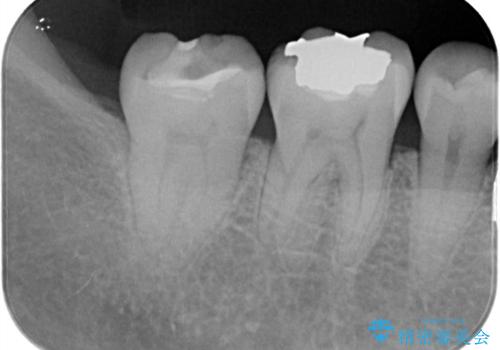

歯間に食渣がつまるのをどうにかしたいとの主訴のもと、治療を開始しました。フロスを通してみると、コンタクトは無く0.25mm程のスペースがありました。

メタルインレーを歯冠色のものに変えたいという希望もあったため、セラミックインレーでのやり替えによるコンタクトの再現をしています。

また、近心側にう蝕が認められたため窩洞の範囲を元々入っていたメタルインレー窩洞よりも広げています。